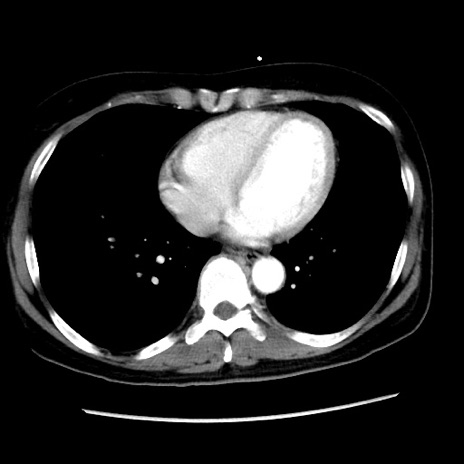

冠状断像

【症例】 50歳代女性

【主訴】 腹痛

【現病歴】前日生レバーを食べた。今朝に排便あり。 昼前に突然発症の腹痛を生じ、当院救急外来を受診した。

【既往歴】 子宮筋腫にてで子宮全摘後

【身体所見】 意識清明、腹部:平坦、軟、下腹部やや左を中心に圧痛・反跳痛あり、筋性防御あり

【データ】WBC 7800、CRP 0.07